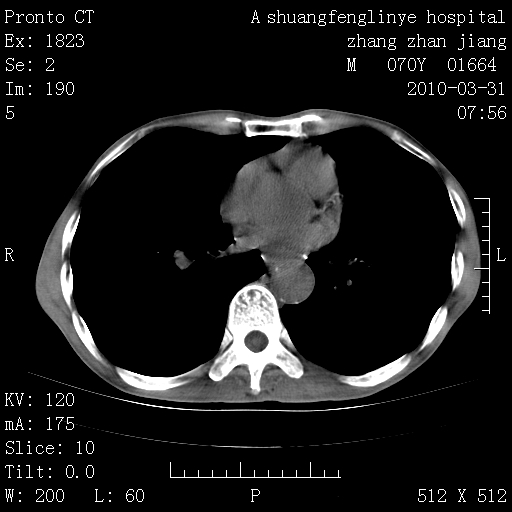

标题: CT25450:肺结核?

双上肺继发型tb并左上空洞形成,主动脉冠脉钙化。

支持:继发性肺结核伴空洞形成!建议纤支镜检查待出外周围型肺癌可能!

1)两肺上叶继发性肺结核并左肺上叶空洞形成。2)冠状动脉及主动脉钙化。